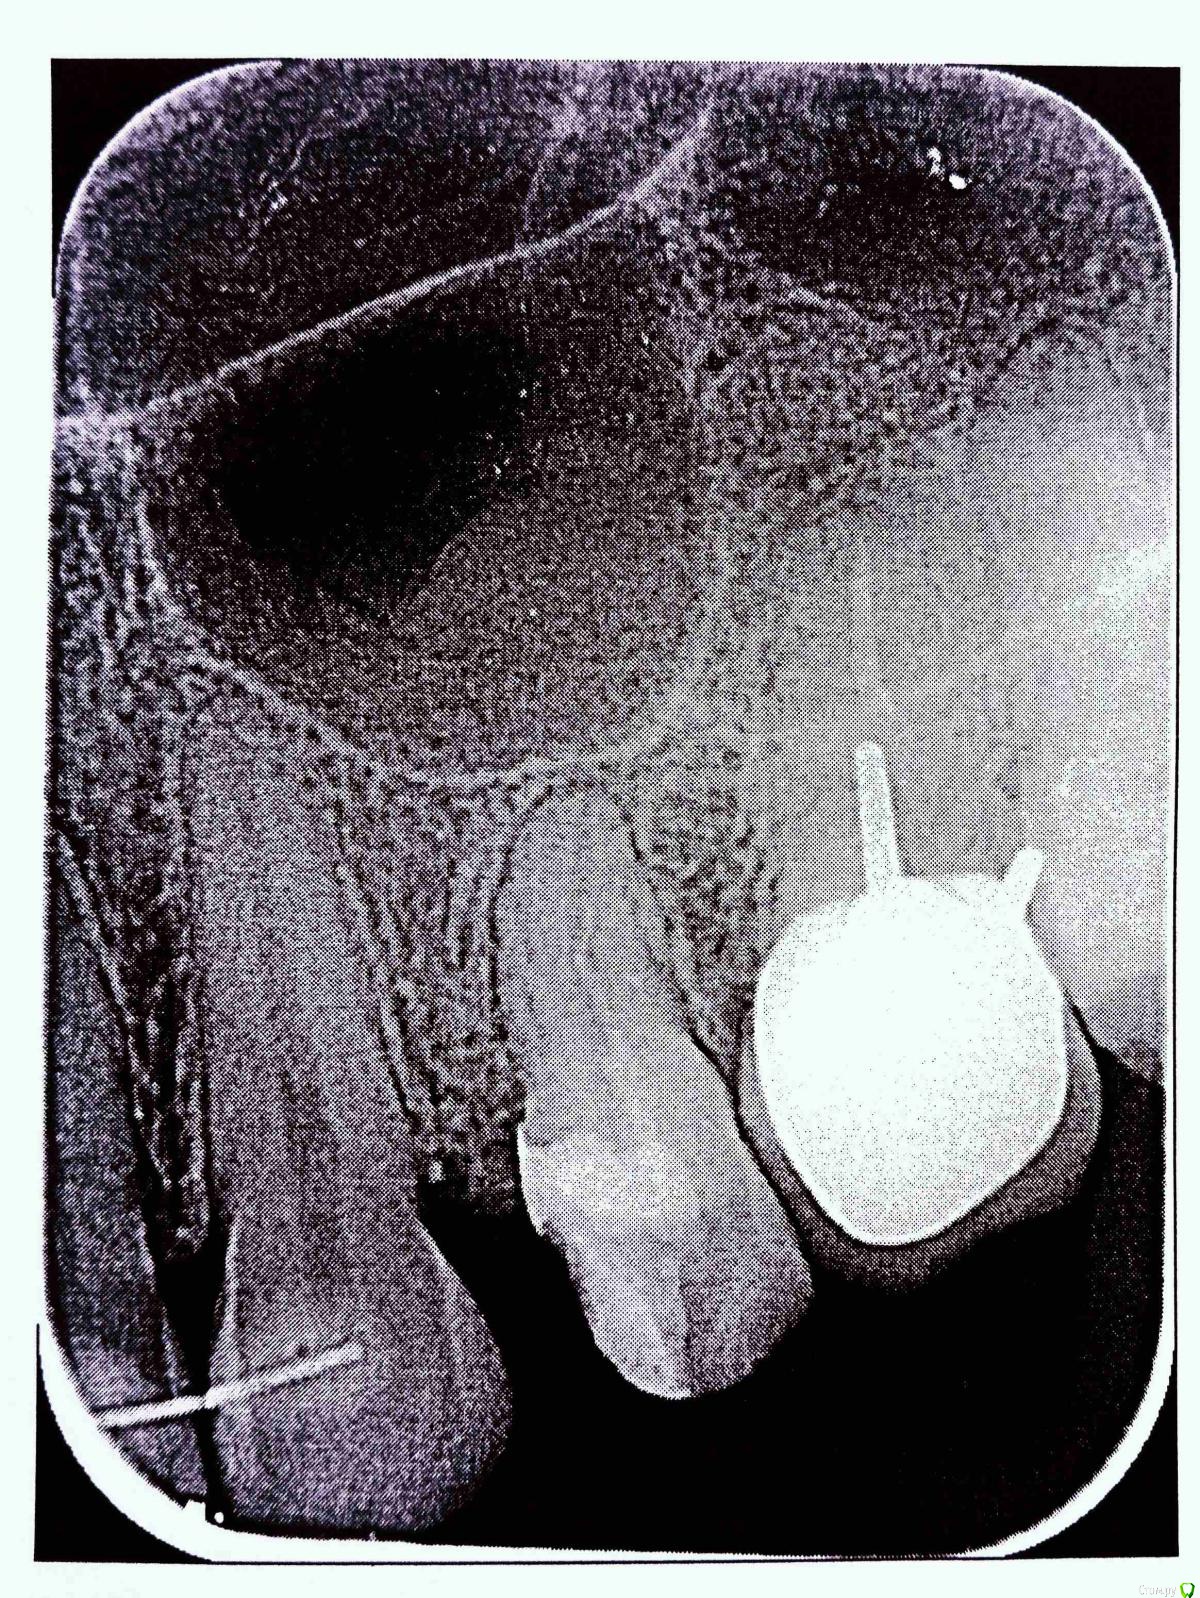

170997 Опубликовано 5 октября, 2019 Поделиться Опубликовано 5 октября, 2019 (изменено) Доброе время суток, уважаемые специалисты,скажите пожалуйста по снимку стоит беспокоиться о выходе пломб.материала? при нажатии зуба боль, лечение 5 дней назад Изменено 5 октября, 2019 пользователем 170997 Ссылка на комментарий

170997 Опубликовано 6 октября, 2019 Автор Поделиться Опубликовано 6 октября, 2019 Снимок до лечения Ссылка на комментарий

shishok Опубликовано 6 октября, 2019 Поделиться Опубликовано 6 октября, 2019 Не беспокойтесь, ничего страшного. Ссылка на комментарий

red_butler Опубликовано 7 октября, 2019 Поделиться Опубликовано 7 октября, 2019 Спасибо за ответ, а гайморовая пазуха не задета?или могут позже проявиться последствия ?Не задета Ссылка на комментарий

St. Опубликовано 8 октября, 2019 Поделиться Опубликовано 8 октября, 2019 Боль постепенно успокоится, нужно подождать, а пока старайтесь не нагружать эту сторону при жевании. Выведение материала минимальное и ни на что не влияет в таком количестве Ссылка на комментарий

red_butler Опубликовано 8 октября, 2019 Поделиться Опубликовано 8 октября, 2019 И обязательно восстановите зуб искусственной коронкой, иначе хрюм... и всё Ссылка на комментарий